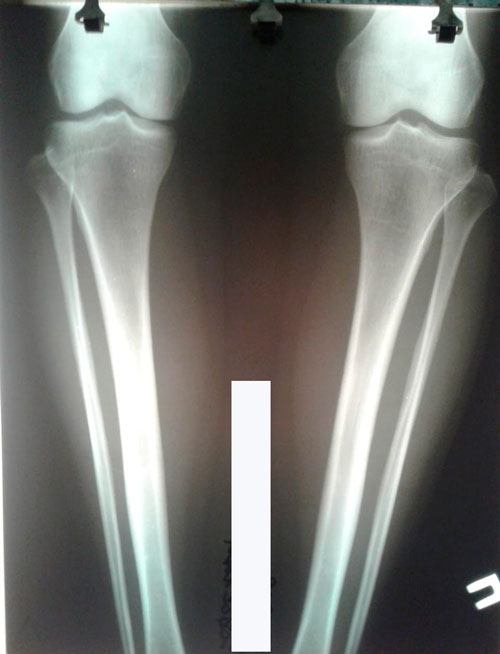

Исходник -29 лет.Астана

Дата операции- 19.09.2018г.

Дата снятия аппаратов -27.12.2018.

Срок сращения - 97 дней.